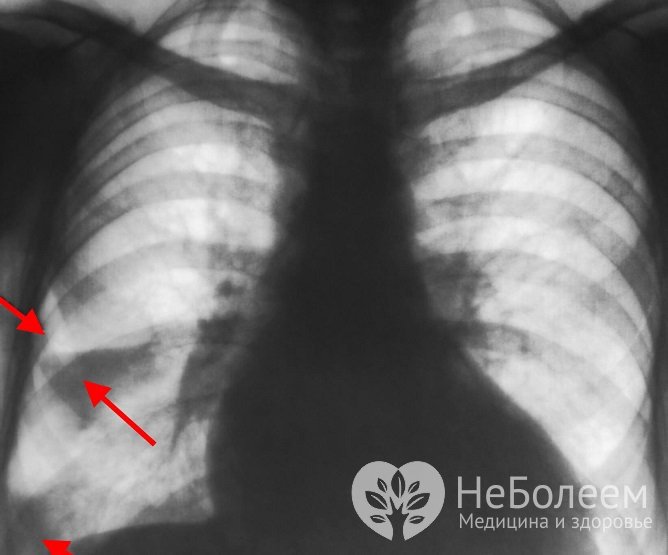

Основными рентген-признаками заболевания является расширение, деформация и усиленная васкуляризация корня легкого, участок повышенной плотности в форме клина, который вершиной направлен к корню легкого, а основой к периферии. Возможно наличие выпота в плевральной полости при длительном течении заболевания.